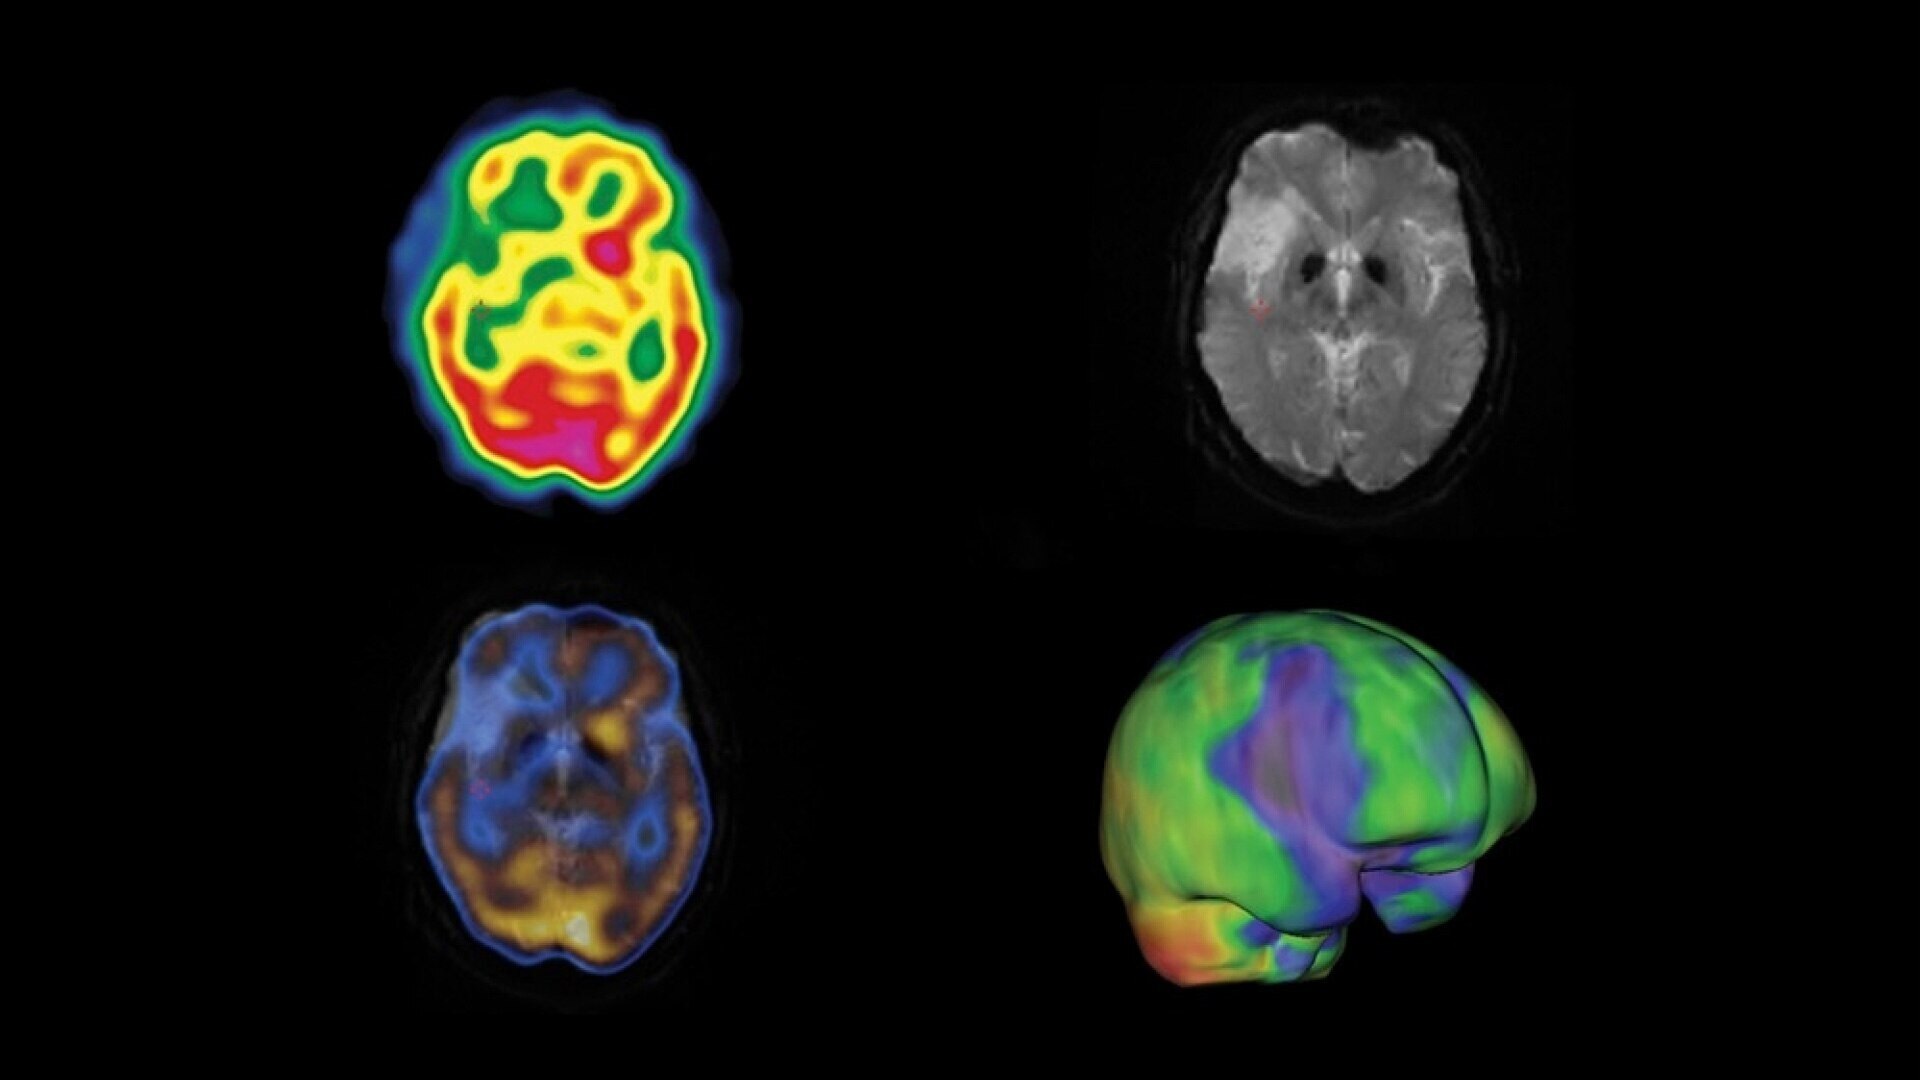

Built for Quantitation

Quantitative SPECT/CT for every patient, every day

NM/CT 870 CZT is a SPECT/CT built for consistent, reproducible quantitation. Improvements to detector performance enable exceptional spatial and energy resolution. It also leverages CT-based attenuation and scatter correction along with Evolution3 image reconstruction. In addition, ever-increasing computational power enables precise camera calibration for less variation between exams.

Once your quantitative studies are acquired, SmartConsole - together with Xeleris - makes it easier to access them. Your quantitative SPECT/CT studies are automatically transferred directly to the PACS or other pre-defined DICOM destinations. An additional dataset in PET DICOM format allows you to review and evaluate images on the same devices you use to view your PET/CT studies, as adjacent information to the original SPECT/CT images.

See everything clearly now

As molecular imaging continues to move toward the development of disease-specific diagnoses and increasingly personalized care, resolution is important. Early disease detection is only possible with a high system resolution that enables visualization of finer anatomic detail.

The resolution to discover something new

With direct conversion detection, NM/CT 870 CZT has substantially improved system resolution⁴ by eliminating the signal loss and noise that comes with analog detection technology. It also uses a registered collimation design that aligns each collimator hole with a single detector pixel. This design eliminates the impact of collimator resolution that would normally affect the overall system resolution. The result is an improved contrast-to-noise ratio⁵ and spatial resolution down to 2.8 mm.⁶